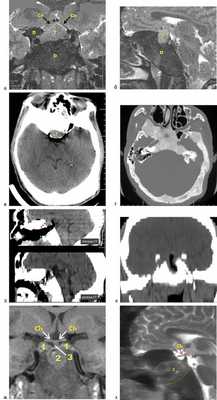

При обследовании в Национальном медицинском исследовательском центре нейрохирургии им. акад. Н.Н. Бурденко обнаружены аденома гипофиза; акромегалия, активная фаза; хиазмальный синдром; синдром МакКьюна—Олбрайта; полиоссальная фиброзная дисплазия в виде поражения костей свода и основания черепа, кожная пигментация по типу пятен «кофе с молоком». Выявлены также гормонально-неактивные новообразования обоих надпочечников.

Поражение основной кости носило асимметричный характер в виде утолщения ее крыльев и переднего наклоненного отростка справа, правой половины решетчатой кости, ската тела основной кости вплоть до рострума. Полость пазухи основной кости отсутствовала. Нами произведено эндоскопическое эндоназальное транссфеноидальное удаление эндосупраселлярной опухоли гипофиза. С использованием навигации («BrainLab», Германия) различными борами выполнена туннелеобразная трепанация по средней линии в толще резко утолщенной кости, измененной вследствие дисплазии. В результате существенной погрешности навигации по вертикали первоначально удалось выйти на развилку основной артерии. Горизонтально расположенная ТМО над местом обнаружения основной артерии представлялась «дном» турецкого седла, однако при рассечении ТМО обнаружена ткань, более всего напоминавшая мозговое вещество. Одновременно справа от средней линии обнаружен небольшой темный узел ткани, которая, будучи покрытой ТМО, более всего напоминала венозный синус. При рассечении ТМО обнаружена ткань, похожая на опухоль гипофиза, но, учитывая небольшой объем узла и наличие у него костных стенок, поиски турецкого седла решено продолжить. После получения результатов срочной биопсии, подтвердившей, что оба образца тканей являются фрагментами аденомы гипофиза, и после выполнения СКТ, подтвердившей выполнение трепанации строго по средней линии, но непосредственно под дном турецкого седла, трепанация расширена вверх. Обнаружена передняя стенка турецкого седла, из полости которого удалена мягкая синюшного цвета аденома гипофиза. Опухоль распространялась в полость правого кавернозного синуса, где после ее аспирации обнаружено заднее колено сонной артерии. В полость синуса уложена гемостастическая марля, в турецкое седло и на стенки образовавшейся полости уложена гемостатическая губка Тахокомб («Linz», Австрия). На дефект ТМО в области основной артерии уложены лоскут аутофасции, фрагмент жировой ткани, еще один лоскут фасции, костная пластина от носовой перегородки, еще один фрагмент жировой ткани, укрытый мукопериостальным лоскутом. Слои пластики герметизированы фибрин-тромбиновым клеем.

Гистологическое исследование подтвердило наличие соматотропиномы с высоким уровнем Ki-67 5—6% (см. табл. 4). Послеоперационный период протекал без особенностей. Отмечено улучшение зрительных функций (см. табл. 3). При осмотре оториноларингологом назальная ликворея не выявлена.

При контрольной МРТ через 3 мес после операции отмечено формирование «пустого турецкого седла». Инфраселлярно в сформированном в утолщенной кости дефекте сохраняется пластический материал. В области обоих кавернозных синусов — небольшие остатки опухоли, что объясняет отсутствие клинико-биохимической ремиссии заболевания (см. табл. 2, см. рис. 3). Рис. 3. Клинический случай 2. а, б — картина, полученная при МРТ до операции; в, г — картина, полученная при СКТ до операции; д — интраоперационная картина СКТ: до (верхнее изображение) и после (нижнее изображение) выполнения дополнительной резекции кости в области передней стенки турецкого седла; е — картина, полученная при СКТ после операции; ж, з — картина, полученная при МРТ после операции. Т или 1 — опухоль; D — очаг фиброзной остеодисплазии; Ch — хиазма; 2 — зона резецированной измененной дисплазией кости; 3 — стебель гипофиза. Пациенту рекомендовано проведение лучевой терапии на область остаточной опухоли.

В наших наблюдениях клинические проявления синдрома МакКьюн—Олбрайта носили классический характер. Размер и расположение аденом гипофиза, вне зависимости от состояния пораженных костей основания черепа, определяли выбор трансназального доступа как оптимального для достижения максимально полного и безопасного удаления. Остеодиспластические изменения основной кости у пациентов были различной степени выраженности. В обоих случаях поражение основания черепа было асимметричным, но в 1-м случае полость основной пазухи и анатомические ориентиры на контралатеральных пораженных костях сохранены, что позволило, ориентируясь по ним, резецировать пораженную кость до получения доступа к турецкому седлу.

Во 2-м случае никаких анатомических ориентиров не сохранилось — резекция кости была возможна только под навигационным контролем. Отсутствие ошибки по горизонтали позволило не потерять ориентир средней линии. Ошибка по вертикали стала причиной того, что на первом этапе операции кость резецирована вплоть до ската ТМО, но под турецким седлом. Только выполнение этапной компьютерной томографии позволило сориентироваться и выполнить доступ к опухоли без интраоперационных осложнений. Для быстрой и безопасной резекции уплотненной кости во 2-м случае потребовалось использовать нетрадиционный для трансназальной хирургии инструмент — пневматическую дрель с борами увеличенного диаметра (5—6 мм).